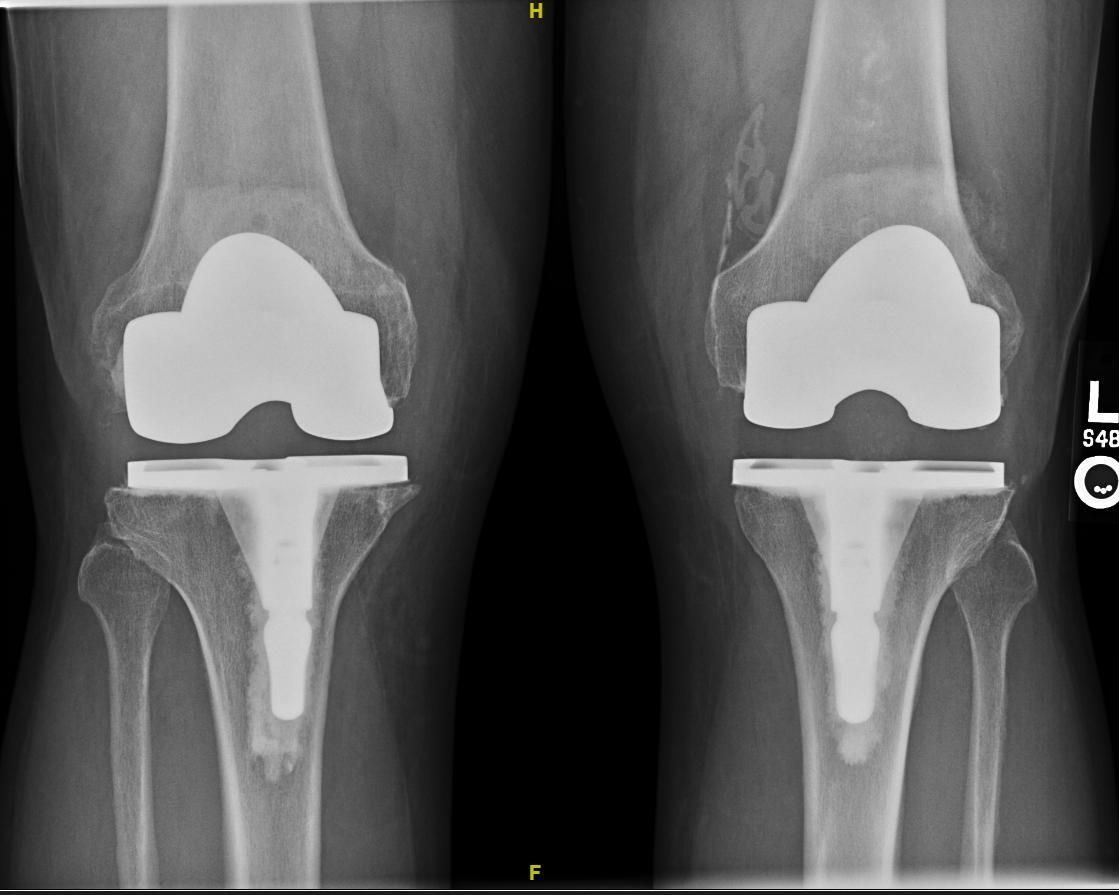

您好!我是北京積水潭醫(yī)院唐浩醫(yī)生?!拔业娜斯りP(guān)節(jié)到底能用多久?”,“怎樣才能讓人工關(guān)節(jié)用的時間更長一些?”,是每一個關(guān)節(jié)置換患者都會問我的重要問題。對每一位患者朋友來說,從經(jīng)濟、時間、身體上,關(guān)節(jié)置換都是一個重大決策,我們目標(biāo)是實現(xiàn)可以良好使用幾十年的膝關(guān)節(jié),但是失敗的膝關(guān)節(jié)置換就會需要進行二次翻修手術(shù),而翻修術(shù)后的效果通常不如初次置換那么令人滿意。然而,對這一問題卻無法給每一個特定患者確切的答案,這是因為人工關(guān)節(jié)的壽命受到多方面因素的影響。如果沒有導(dǎo)致關(guān)節(jié)早期失敗的因素,例如感染、不穩(wěn)定、脫位、骨折等,人工關(guān)節(jié)的遠期壽命主要取決于關(guān)節(jié)的磨損速度。這就像汽車輪胎一樣,隨著時間延長、運行公里數(shù)增加,必然會產(chǎn)生輪胎表面的磨損,直至輪胎損壞。人工膝關(guān)節(jié)磨損的原因膝關(guān)節(jié)假體是由金屬與聚乙烯材料制成,這些在運動中相接觸的材料會不可避免的產(chǎn)生劃痕、氧化、剝脫,進而逐漸磨損。對于患者來說,在正規(guī)醫(yī)院進行初次置換術(shù),獲得良好的初次手術(shù)效果,對于延長人工膝關(guān)節(jié)的壽命,是非常重要的。大多數(shù)患者都知道膝關(guān)節(jié)假體會在使用中產(chǎn)生磨損,但是膝關(guān)節(jié)的磨損速度跟很多因素相關(guān),以下我們逐一進行介紹。要向延長假體使用壽命,首要的因素是要避免并發(fā)癥的發(fā)生,因為一旦發(fā)生了嚴重并發(fā)癥,就需要進行二次翻修手術(shù)。這就類似買一輛好車,需要避免交通事故才能開的久的道理一樣。我們患者朋友可預(yù)防的術(shù)后并發(fā)癥,主要包括兩項:假體周圍感染、假體周圍骨折。如何預(yù)防假體周圍感染?假體周圍感染是由于在人工關(guān)節(jié)表面出現(xiàn)了細菌定植,形成了關(guān)節(jié)化膿。術(shù)后遠期假體感染的發(fā)生絕大多數(shù)不是關(guān)節(jié)外傷引起的創(chuàng)傷性感染,而是由于其他部位的感染,引起了細菌入血,從而使得細菌在全身循環(huán),由于人工關(guān)節(jié)本身沒有免疫力,特別容易導(dǎo)致細菌定植在人工關(guān)節(jié)引起假體周圍感染。因此,任何其他部位的感染,都是需要預(yù)防的高風(fēng)險因素。例如,拔牙等口腔科侵入性治療、呼吸道感染、皮膚感染、腳氣、痔瘡等;這些操作或者其他部位感染發(fā)生時,需要使用2-3天抗生素,來預(yù)防細菌隨血液循環(huán)進入關(guān)節(jié)腔。常選用的抗生素是廣譜殺菌的二代頭孢菌素,例如頭孢呋辛。如何預(yù)防假體周圍骨折?首先是避免術(shù)后外傷,例如跌倒、車禍、高處墜落、碰撞等外傷的因素。其次是防治骨質(zhì)疏松。嚴重骨質(zhì)疏松的患者,在平地跌倒都可能造成骨折。通過日常規(guī)律鍛煉、口服藥物等方法,可以提高骨的強度,并有效減少假體周圍骨折的風(fēng)險。多少歲對膝關(guān)節(jié)置換來說是年輕?我們通常認為<50歲為膝關(guān)節(jié)置換的年輕患者。年輕患者的活動量更大,理論上對于假體造成的磨損更快,小于50歲的患者在未來進行二次翻修手術(shù)的可能性會增加。文獻表明,<50歲患者的全膝關(guān)節(jié)置換假體20年生存率約為75%-80%。雖然如此,有絕對適應(yīng)癥的年輕患者,我們也積極主張進行手術(shù)重建,因為大部分年輕患者(70-80%)通過一次手術(shù)可獲得20年以上的高質(zhì)量生活。這20年的健康生活和工作能力,對于個人、家庭、親人來說都是極其寶貴的。如果忍耐20年,不僅會在人生的青壯年關(guān)鍵時期生活質(zhì)量、經(jīng)濟收入都會受到極大損失,您的關(guān)節(jié)病變也會變得極其嚴重,導(dǎo)致手術(shù)費用成倍上漲,置換手術(shù)的效果也常常不理想。研究表明,肥胖患者膝關(guān)節(jié)假體的使用壽命越短。多少體重算肥胖呢?世界衛(wèi)生組織用體重指數(shù)(Bodymassindex,BMI)來定義肥胖,BMI=體重(公斤)÷身高(米)的平方。研究表明,當(dāng)體重指數(shù)超過30時,膝關(guān)節(jié)假體的使用壽命會明顯縮短。因此,維持合適的體重對于延長假體的壽命來說至關(guān)重要。適量的運動對于維持膝關(guān)節(jié)假體的健康非常有幫助。通常推薦患者進行免負重的體育鍛煉,例如游泳、自行車等等,既促進了關(guān)節(jié)功能康復(fù),又控制了體重。正常的日常生活,例如走路、上下樓梯,不會影響假體使用壽命。而過度的活動會造成膝關(guān)節(jié)假體應(yīng)力過大,帶來聚乙烯假體的磨損。隨著人們越來越多的重視體育運動,很多患者問術(shù)后是否能恢復(fù)體育鍛煉?我們的回答是,恢復(fù)健康運動生活恰恰是我們進行關(guān)節(jié)重建的目的之一,同時,適當(dāng)運動可以幫我們控制體重,延長假體的使用壽命。因此,適度運動對于維持關(guān)節(jié)功能、促進康復(fù)是有極大好處的,不需要進行限制。那哪些術(shù)后運動是推薦的呢?我們的原則是選擇可以促進關(guān)節(jié)活動,同時減少關(guān)節(jié)負重的運動,最佳的運動是游泳、騎自行車等。很多患者朋友說我不會游泳、騎車怎么辦?那么其他低強度運動例如跳廣場舞、慢跑、高爾夫球等,對于恢復(fù)關(guān)節(jié)功能也非常好,不會造成膝關(guān)節(jié)假體失敗。而對于高強度體育運動,例如馬拉松長跑、競技性足球、滑雪、籃球比賽等,患者則應(yīng)聽取手術(shù)醫(yī)生的意見進行綜合判斷。醫(yī)生會根據(jù)術(shù)中膝關(guān)節(jié)的穩(wěn)定性的不同,選擇合適患者的關(guān)節(jié)假體。根據(jù)假體結(jié)構(gòu)對膝關(guān)節(jié)活動的限制程度,人工膝關(guān)節(jié)假體可以分為表面置換假體、半限制性假體以及鉸鏈型膝關(guān)節(jié)假體。表面置換型假體根據(jù)是否保留后交叉韌帶,又分為后交叉韌帶保留性、后交叉韌帶替代型兩大主流設(shè)計。大多數(shù)初次膝關(guān)節(jié)置換術(shù)使用表面置換型假體即可完成,半限制性、鉸鏈型假體是在膝關(guān)節(jié)周圍韌帶存在嚴重缺損,或關(guān)節(jié)存在嚴重畸形,不能實現(xiàn)關(guān)節(jié)軟組織平衡的情況下才需要使用。限制程度越高,假體在活動中所承受的應(yīng)力越大,越容易出現(xiàn)磨損、松動等問題。因此,使用髁限制型假體、鉸鏈型的患者更應(yīng)該避免增加關(guān)節(jié)內(nèi)應(yīng)力的劇烈活動。假體的材料、制作工藝是對假體的磨損速度存在顯著影響的。所有人工膝關(guān)節(jié)假體都包括股骨假體和脛骨側(cè)平臺兩部分,其中股骨側(cè)為鈷鉻鉬合金材料,脛骨側(cè)為金屬平臺上放置的聚乙烯墊片材料。聚乙烯材料用于人工膝關(guān)節(jié)脛骨墊片已有超過40年歷史,成為膝關(guān)節(jié)置換的標(biāo)準工藝。近年來,添加維生素E等抗氧化劑的聚乙烯逐漸應(yīng)用,具有降低聚乙烯磨損的作用。股骨側(cè)的金屬表面拋光度對于磨損有很大影響。盡管陶瓷界面在髖關(guān)節(jié)置換中已得到廣泛應(yīng)用,但在膝關(guān)節(jié)置換中,由于股骨假體厚度限制,陶瓷的脆性使其尚不能替代金屬材料。氧化鋯處理的金屬表面是在鈷鉻鉬合金的表面形成一層氧化鋯的硬化層,這樣不僅保持了金屬假體的柔韌性,同時獲得了類似陶瓷材料的耐磨性能,是很有前景的膝關(guān)節(jié)假體摩擦界面。

您好!我是北京積水潭醫(yī)院矯形骨科唐浩醫(yī)生,為了便于您更好的了解關(guān)節(jié)置換手術(shù)的基本知識,我們將患者的常見問題整理出來,供您參考,祝您就醫(yī)愉快、早日康復(fù)!正常的關(guān)節(jié)活動時,關(guān)節(jié)內(nèi)的軟骨可以有效減少骨與骨之間的摩擦。當(dāng)發(fā)生骨性關(guān)節(jié)炎等疾病時,軟骨老化、變形,骨與骨之間的摩擦加劇,引起關(guān)節(jié)腫脹、疼痛、變形。人工關(guān)節(jié)置換術(shù)是將損壞的關(guān)節(jié)軟骨切除,在經(jīng)過修整的骨表面安裝金屬假體和耐磨的人工材料。這樣,關(guān)節(jié)活動時,關(guān)節(jié)假體之間的摩擦代替了骨與骨之間的摩擦,從而使患者的下肢畸形得到矯正、癥狀得到緩解,從而關(guān)節(jié)功能得到改善、生活質(zhì)量得到提高。人工髖關(guān)節(jié):根據(jù)是否進行髖臼側(cè)置換,分為半髖關(guān)節(jié)置換和全髖關(guān)節(jié)置換。半髖關(guān)節(jié)置換:僅置換股骨頭側(cè),髖臼側(cè)正常的骨、軟骨、盂唇等結(jié)構(gòu)保留。主要用于股骨頸移位骨折、股骨頭粉碎骨折等疾病。相對于全髖置換,其優(yōu)缺點如下:優(yōu)點:手術(shù)簡單、失血量相對全髖更??;缺點:①長期使用后會導(dǎo)致髖臼側(cè)軟骨繼發(fā)磨損、疼痛,可能需要二次翻修為全髖;②對于股骨前傾角異常、髖臼發(fā)育不良、髖臼前傾角異常的患者,半髖置換無法優(yōu)化髖臼側(cè)角度和股骨頭的覆蓋,術(shù)后脫位的風(fēng)險比全髖置換要高。全髖關(guān)節(jié)置換:對股骨頭、髖臼側(cè)都進行置換。優(yōu)點:遠期療效較半髖置換更好;可改變髖臼側(cè)的不利因素,降低術(shù)后脫位風(fēng)險;缺點:比半髖置換手術(shù)出血量更多。因此,對于髖關(guān)節(jié)置換,除非是高齡股骨頸骨折、不能耐受長時間手術(shù)的患者,大多數(shù)建議選擇全髖關(guān)節(jié)置換。人工膝關(guān)節(jié):根據(jù)置換的部位,分為部分關(guān)節(jié)置換術(shù)和全膝關(guān)節(jié)置換術(shù)。膝關(guān)節(jié)部分置換術(shù):人體膝關(guān)可分為內(nèi)側(cè)間室、外側(cè)間室、髕股關(guān)節(jié)三個部分,部分置換術(shù)僅置換其中1或2部分關(guān)節(jié);又可具體分為膝關(guān)節(jié)單髁置換術(shù)(UKA)、髕股關(guān)節(jié)置換術(shù)(PFJ),或聯(lián)合UKA+PFJ的雙間室置換術(shù)。優(yōu)點:手術(shù)創(chuàng)傷相對全膝置換更小,術(shù)后恢復(fù)快、功能好。缺點:①不適用于三個間室都病變的患者、內(nèi)外翻畸形/屈膝畸形嚴重的患者;②存在膝關(guān)節(jié)炎繼續(xù)發(fā)展的可能;③單髁置換假體翻修率比全膝關(guān)節(jié)置換要高。膝關(guān)節(jié)單髁置換術(shù):僅置換膝關(guān)節(jié)發(fā)生關(guān)節(jié)炎的內(nèi)側(cè)或者外側(cè)間室,其他部分保留不動。髕股關(guān)節(jié)置換術(shù):僅置換髕股關(guān)節(jié),適用于單獨并髕股關(guān)節(jié)退變的患者,其他部分保留不動。雙間室置換術(shù):同時行單髁置換+髕股關(guān)節(jié)置換,適用于雙間室關(guān)節(jié)炎的患者。全膝關(guān)節(jié)置換術(shù):對膝關(guān)節(jié)所有三個間室都進行置換。人工關(guān)節(jié)采用金屬和高分子塑料,按照人體關(guān)節(jié)的形狀制作而成。這些材料經(jīng)過嚴格的實驗檢測,是安全可靠的。以下是權(quán)威的國際人工關(guān)節(jié)登記中心的隨訪數(shù)據(jù):全膝關(guān)節(jié)置換:在運動量不大的老年人,全膝關(guān)節(jié)置換的20年生存率為90%-95%;年輕患者的20年假體生存率為80%左右;膝關(guān)節(jié)單髁置換10年假體生存率約為85%~90%。全髖關(guān)節(jié)置換術(shù)的30年生存率約為85%~90%;關(guān)于膝關(guān)節(jié)置換、髖關(guān)節(jié)置換假體使用壽命,請進一步看我的專題文章《我的人工膝關(guān)節(jié)能用多少年?》《我的人工髖關(guān)節(jié)能用多少年?》總的來說,大部分髖膝關(guān)節(jié)嚴重疾病,都可以采用人工關(guān)節(jié)置換術(shù)治療,可以有效緩解關(guān)節(jié)疼痛,糾正關(guān)節(jié)畸形,改善關(guān)節(jié)活動度,同時減輕相鄰關(guān)節(jié)的癥狀,例如腰痛、對側(cè)關(guān)節(jié)痛等。典型的疾病種類例如:(1)退行性骨關(guān)節(jié)病造成的關(guān)節(jié)畸形或關(guān)節(jié)破壞;(2)先天性髖關(guān)節(jié)脫位繼發(fā)嚴重骨性關(guān)節(jié)炎;(3)股骨頭無菌性壞死晚期;(4)類風(fēng)濕性關(guān)節(jié)炎、強直性脊柱炎引起的關(guān)節(jié)功能喪失;(5)老年股骨頸骨折或股骨頸骨折不愈合。我們不光要了解關(guān)節(jié)置換可以治療哪些疾病,也要知道哪些因素是不適合做關(guān)節(jié)置換手術(shù)的。當(dāng)您存在以下情況時,手術(shù)失敗的風(fēng)險非常高,不能做人工關(guān)節(jié)置換術(shù):(1)關(guān)節(jié)活動化膿性感染(2)慢性骨髓炎(3)皮膚、軟組織缺損且傷口不愈合(4)嚴重免疫缺陷(5)全身狀況差,不能耐受手術(shù)麻醉(6)急性心肌梗死<6個月(7)腦卒中<6個月住院以后,我們首先做術(shù)前檢查,評估您的身體狀況、評價心肺功能、制定手術(shù)方案,這大約要2~3天。如果恢復(fù)良好,術(shù)后約3-5天,您就可以出院到康復(fù)中心或在家中進行功能鍛煉。因此,通常關(guān)節(jié)置換手術(shù)的住院時間為5-7天左右。我們的技術(shù)和經(jīng)驗已經(jīng)將手術(shù)時間縮短很多。一般單關(guān)節(jié)置換的手術(shù)時間約60~90分鐘,麻醉準備時間約30分鐘。但如果是關(guān)節(jié)嚴重屈曲變形、關(guān)節(jié)翻修等復(fù)雜手術(shù),手術(shù)時間會延長。膝關(guān)節(jié)置換的傷口長度大約為10-15cm,髖關(guān)節(jié)置換的傷口長度大約為10-12cm。如果關(guān)節(jié)以前嚴重變形,可能傷口還會延長幾公分。人工關(guān)節(jié)置換術(shù)后第1天,患者就要在家屬或護工的幫助下被動的活動關(guān)節(jié)。術(shù)后第2天拔除傷口引流管后,我們即鼓勵患者在床邊練習(xí),下床以助行器或拐杖練習(xí)行走。一般來說,術(shù)后1-2個月可逐漸恢復(fù)日?;顒印4撕?,隨著功能鍛煉的繼續(xù)進行,關(guān)節(jié)的活動會越來越好。(1)停止吸煙這會幫助您降低發(fā)生手術(shù)并發(fā)癥的風(fēng)險。(2)保持積極樂觀的心態(tài)關(guān)節(jié)置換手術(shù)是非常成熟的手術(shù),我們的手術(shù)團隊技術(shù)全面,熟練掌握各類復(fù)雜的關(guān)節(jié)置換和翻修手術(shù)。所以請您放松心情,不要過度緊張。(3)保證良好的身體狀況,避免發(fā)生感染感染可以使細菌在手術(shù)中通過您的身體擴散,感染您新置換的關(guān)節(jié),住院以前要注意避免出現(xiàn)牙齦膿腫、尿路感染、足癬、肺炎和流感等。①如果您患有高血壓、糖尿病等慢性內(nèi)科疾病,建議您住院之前到相應(yīng)的門診進行復(fù)查,請醫(yī)生為您調(diào)整降血壓、降血糖的藥物,使血壓、血糖控制在滿意的水平,這樣手術(shù)更加安全。②腦血管病、冠心病患者請分別到神經(jīng)內(nèi)科、心內(nèi)科門診復(fù)查,評估腦血管、心臟功能。③停用特殊藥物:如果您在家里吃阿司匹林、降壓0號,應(yīng)停藥1星期后方可住院,因為這些藥物會增加手術(shù)出血的風(fēng)險;如果您在使用治療自身免疫病、結(jié)締組織并的生物制劑,例如阿達木單抗、英夫利昔單抗等藥物,應(yīng)停藥至少1個周期,因為這些藥物可能一直免疫力,造成術(shù)后傷口愈合不良甚至感染。術(shù)后疼痛是很多患者擔(dān)心的問題,讓不少患者朋友對手術(shù)治療望而卻步。我要告訴您的好消息是:現(xiàn)在做完人工關(guān)節(jié)置換術(shù)后,已經(jīng)不怎么疼痛了,很多患者朋友也在術(shù)后反饋說,沒有想像的那么疼,這是因為醫(yī)生在圍手術(shù)期大大加強了疼痛管理,包括術(shù)前、術(shù)中、術(shù)后3個方面的主要措施:術(shù)前鎮(zhèn)痛:在術(shù)前,我們會給予關(guān)節(jié)周圍神經(jīng)組織麻醉,可大幅減輕術(shù)后72小時內(nèi)的切口疼痛,北京積水潭醫(yī)院麻醉科在這個領(lǐng)域處于全國領(lǐng)先的地位;術(shù)中鎮(zhèn)痛:手術(shù)中,醫(yī)生會小心操作減少軟組織的創(chuàng)傷,同時會給予術(shù)中“雞尾酒”局部鎮(zhèn)痛藥物在關(guān)節(jié)周圍注射,可以有效控制術(shù)后24-48小時內(nèi)的疼痛;術(shù)后鎮(zhèn)痛:術(shù)后,我們通過口服鎮(zhèn)痛藥、靜脈鎮(zhèn)痛藥系列藥物,控制術(shù)后48-72小時后的疼痛。因此,患者朋友們不必懼怕手術(shù)后疼痛的問題。書接上文,術(shù)后良好的疼痛控制是關(guān)節(jié)康復(fù)鍛煉的基礎(chǔ),只有實現(xiàn)關(guān)節(jié)提供無痛的環(huán)境,才能達到最好的康復(fù)效果!由于NSAIDS、阿片類口服鎮(zhèn)痛藥存在一定的副作用,不少患者朋友擔(dān)心存在止疼藥上癮、傷害身體等副作用,而自行停止服用術(shù)后止疼藥,這對于關(guān)節(jié)康復(fù)鍛煉是非常不利的。第一,對于阿片類(嗎啡等)藥物,醫(yī)療用止痛是不會引起上癮的;第二,當(dāng)有以下三種情況不能服用非甾體抗炎藥(NSAIDS)類的止疼藥:存在嚴重的胃食管等消化道潰瘍、胃炎等疾?。淮嬖趪乐啬I損傷、腎功能不全等;存在心臟功能不全、冠心病等情況。如果存在以上三類情況,您需要告知醫(yī)生,調(diào)整您的術(shù)后藥物鎮(zhèn)痛方案。因此,對于沒有以上高危因素的患者,在術(shù)后對于醫(yī)生開的口服鎮(zhèn)痛藥,一定要按時、足量服用,才能達到最好的康復(fù)鍛煉效果!